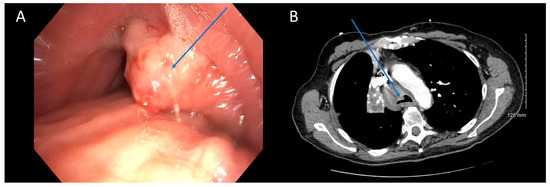

Our analysis revealed moderate to good agreement between bronchoscopy and CT regarding the subtype of obstruction (81% agreement, Cohen’s κ = 0.683, p < 0.001). There was excellent concordance between the two modalities when subtype was identified as extrinsic (15/17, 88%) or intrinsic (24/27, 89%) on bronchoscopy. The primary area of disagreement was that a number of cases were characterized as extrinsic disease on CT (13/60, 22%) when they were mixed on bronchoscopy. One possible explanation is that bronchoscopy may unveil features not easily discernible on CT scans. It is possible that extrinsic and mixed obstruction exist on a spectrum, with luminal wall edema and luminal wall tumor infiltration existing in obstruction that is more heavily extrinsic, but still with some mixed component [26]. Bronchoscopy’s ability to detect these nuances enables a classification of mixed subtype, which may not be as evident on standard 5 mm CT scans (Figure 2). Higher resolution CT scans with virtual bronchoscopy reconstruction might enhance the identification of such subtleties [27]. In a previous study by Naidich et al., CT scans were found to accurately identify focal airway lesions with 90% accuracy. However, the study concluded that axial CT scans were inaccurate in predicting whether the abnormality would be endobronchial, submucosal, or extrinsic [28]. Finkelstein et al. conducted a study involving 44 patients using super high-resolution CT scanning, revealing sensitivities for the detection of endoluminal, obstructive, and mucosal lesions at 90%, 100%, and 16%, respectively [29]. Another retrospective study by Mamatha et al., involving 426 patients, found the sensitivity of CT in detecting abnormal mucosa, endobronchial masses, and extrinsic compression to be 27.50%, 89.00%, and 59.52%, respectively [30]. Although these studies primarily focused on identifying focal airway abnormalities in both healthy and diseased patients, rather than specifically characterizing central airway obstruction, a consistent trend emerges indicating poor characterization of mucosal lesions. This aligns with our observations that mixed diseases with predominantly extrinsic component might be erroneously interpreted solely as extrinsic on CT due to its inability to detect mucosal abnormalities. Mixed disease should be less prone to being misinterpreted as intrinsic disease, since intrinsic airway compression should be recognizable on both imaging and bronchoscopy, consistent with our findings. Based on the above findings, we recommend exercising caution when extrinsic disease is identified on CT scans, as there is a risk of overlooking potential intrinsic disease components. We advocate for maintaining flexibility in treatment approaches, particularly by considering bronchoscopy for further evaluation when extrinsic disease is suspected based on CT findings.

Figure 2. CT is Poor at Identifying Mucosal Component of Malignant Central Airway Obstruction. Bronchoscopic (A) and CT (B) images illustrating malignant central airway obstruction in the right main stem bronchus of the same patient. The CT image suggests primarily extrinsic obstruction, whereas bronchoscopy reveals a combination of extrinsic and intrinsic disease (mixed subtype). Arrows in blue indicate the tumors, while the black circle in (A) highlights the mucosal edema visible during bronchoscopy.